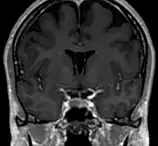

Septum pellucidum

Le septum pellucidum, est une membrane verticale, fine, triangulaire séparant les cornes antérieures des 2 ventricules latéraux du cerveau, passant du corps calleux jusqu'au fornix.

Le septum pellucidum est situé sur la ligne médiane du cerveau, entre les deux hémisphères cérébraux. Il est attaché en haut au corps calleux, l'ensemble des fibres nerveuses qui connectent les 2 hémisphères. En arrière il est en rapport avec la partie antérieure du fornix, et de part et d'autre on trouve la face médiane des deux ventricules latéraux.